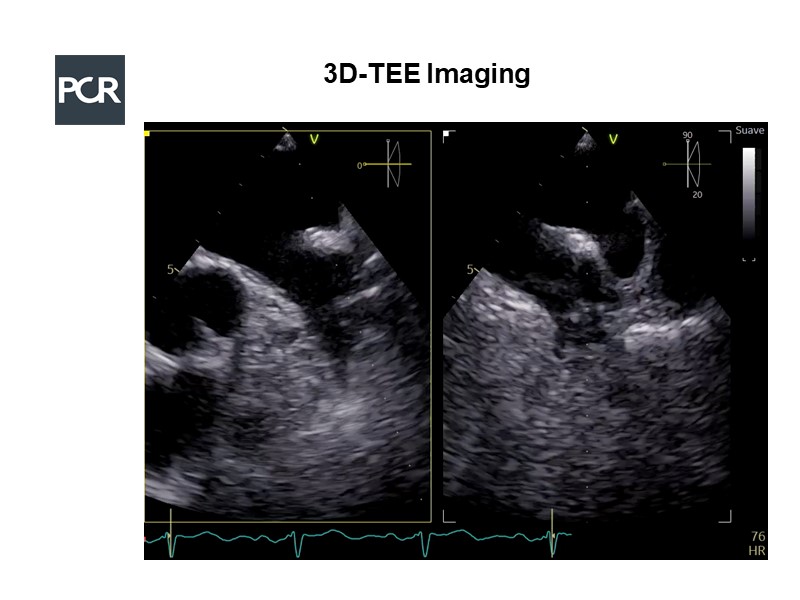

Imaging in LAA occlusion: from planning to final assessment

Consult this session to learn about imaging supporting LAA occlusion procedure, how to combine different imaging techniques to guide this intervention and their value for procedure planning.